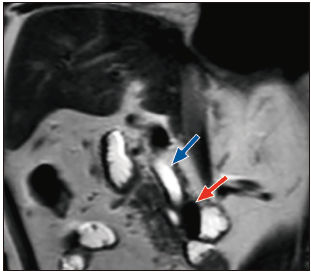

Paciente varón de 82 años, admitido en el servicio de emergencias del hospital, con un tiempo de enfermedad de dos semanas de evolución, caracterizado por dolor abdominal en el cuadrante superior derecho (CSD), fiebre e ictericia en escleras. En la exploración física se destacó la presencia de ictericia en escleras y la presencia de dolor a la palpación en CSD, con signo de Murphy negativo. Los análisis de laboratorio mostraron: recuento de leucocitos 18.7x109/L con 8% de abastonados, proteína C reactiva (PCR) 6,54 mg/dl, bilirrubina total 4,74mg/dl (bilirrubina directa 2,48mg/dl), TGO 382 U/L, TGP 377 U/L, fosfatasa alcalina 167 U/L, gamma-glutamil-transpeptidasa 1044 U/L y albúmina 2,7g/dl. La CPRM reveló una dilatación del conducto biliar común y del conducto pancreático principal a nivel de la cabeza del páncreas, sin evidencia de lesiones, y un divertículo de 23 x 21 mm a nivel de la segunda porción duodenal. No se observó dilatación de la vía biliar intrahepática ni evidencia de litos en la vía biliar o en la vesícula biliar (Figura 1).

Figura 1. Colangiopancreatografía por resonancia magnética, que muestra un

divertículo duodenal periampular (flecha roja) y dilatación del conducto biliar común (flecha

azul).